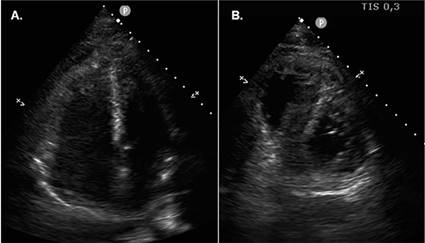

presenta nuevo episodio sincopal. Se realiza un ecocardiograma transtorácico (ETT) Doppler (Figura 1) con evidencia de dilatación de cavidades derechas; por

lo que, asociado al antecedente reciente de cirugía traumatológica, se sospecha

Fig. 1. Ecocardiograma transtorácico

al ingreso. A. Vista apical de 4 cámaras, fin de sístole. Se observa marcada

dilatación de cavidades derechas. B. Eje corto paraesternal.

Se observa la dilatación del ventrículo derecho, con aplanamiento del septum

interventricular.